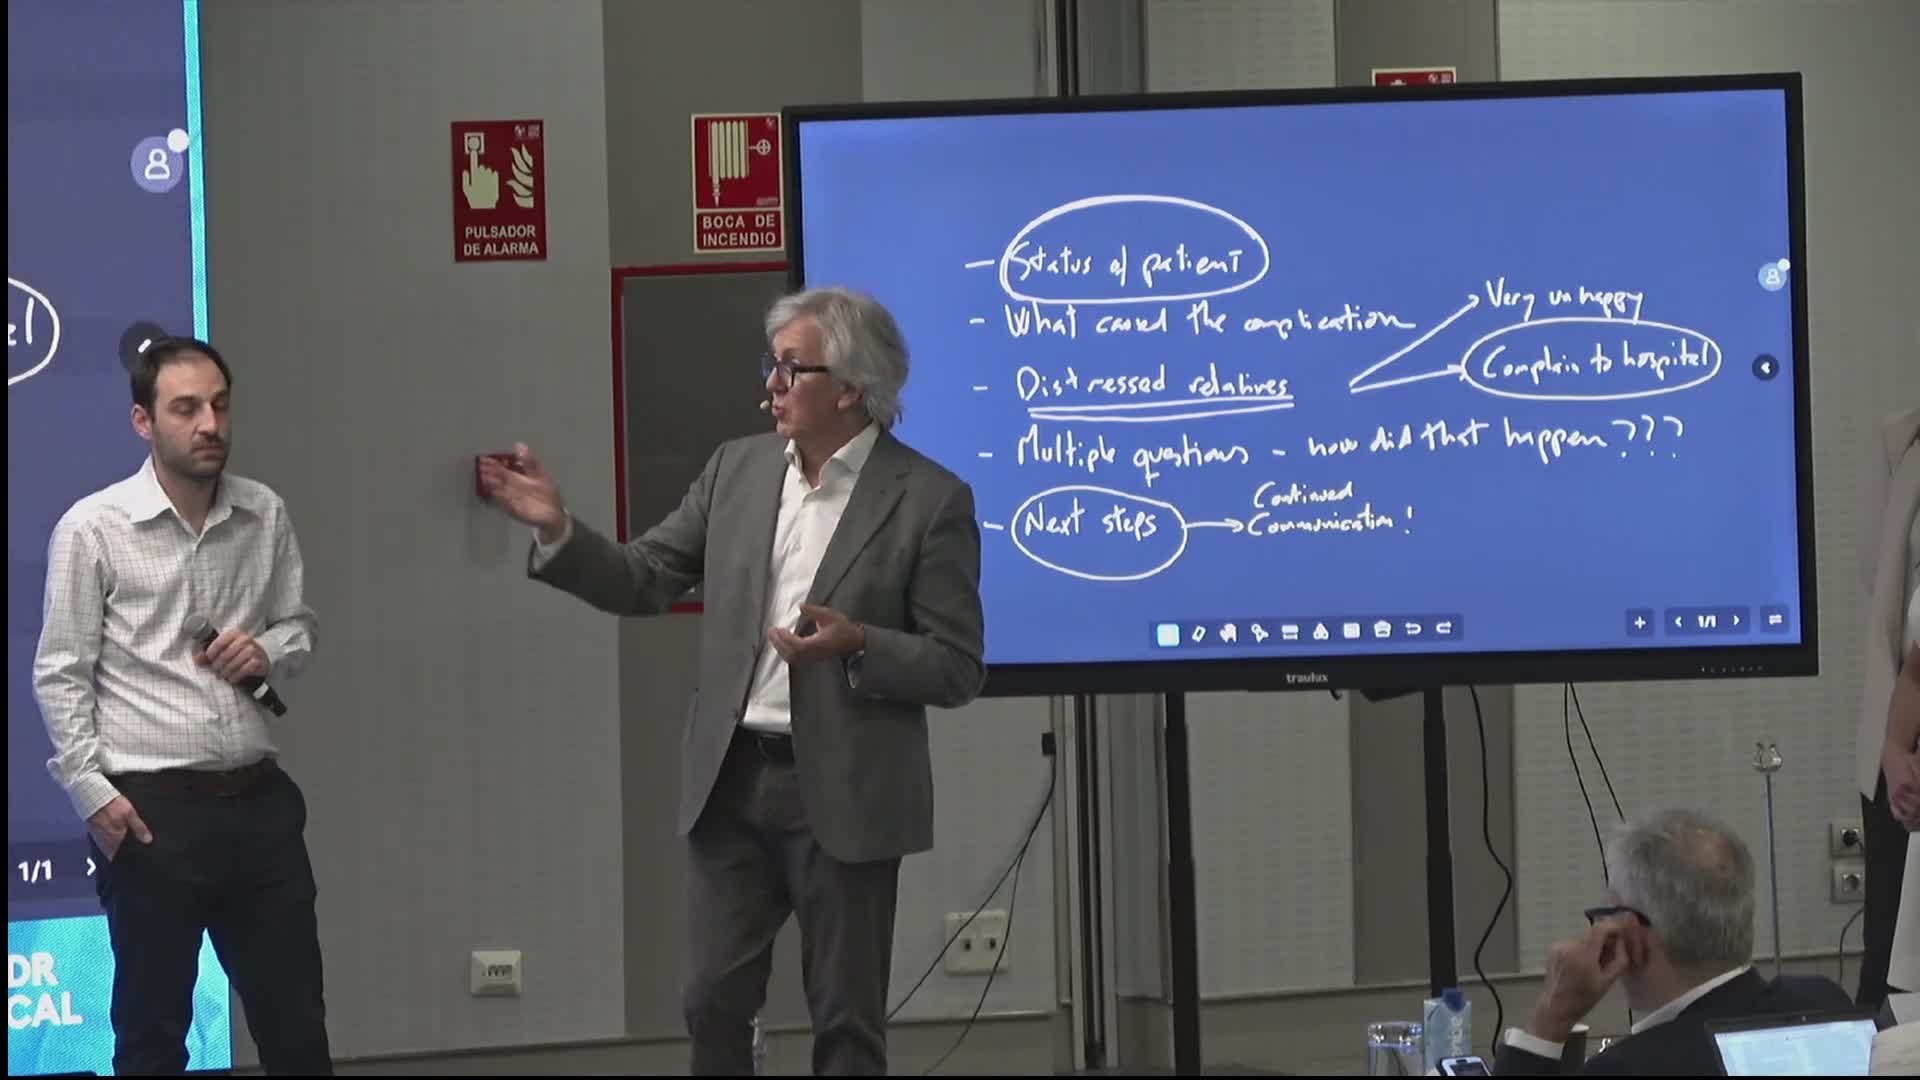

Recognise Post Angiography Problems Early and Treat Decisively - Ricardo Petraco